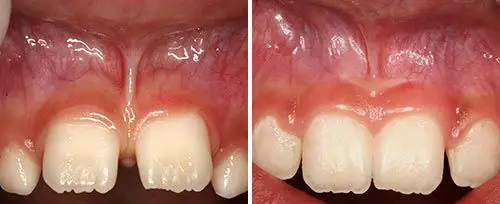

Frenectomy Treatment